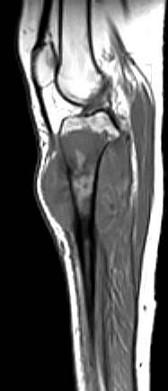

问题 男,35岁,胫骨中上段剧烈疼痛,尤以夜间明显,可摸到肿物,请结合图像,选择最佳选项 ( )

选项 A、骨肉瘤 B、骨巨细胞瘤 C、软骨肉瘤 D、骨转移瘤 E、软骨瘤

答案 A